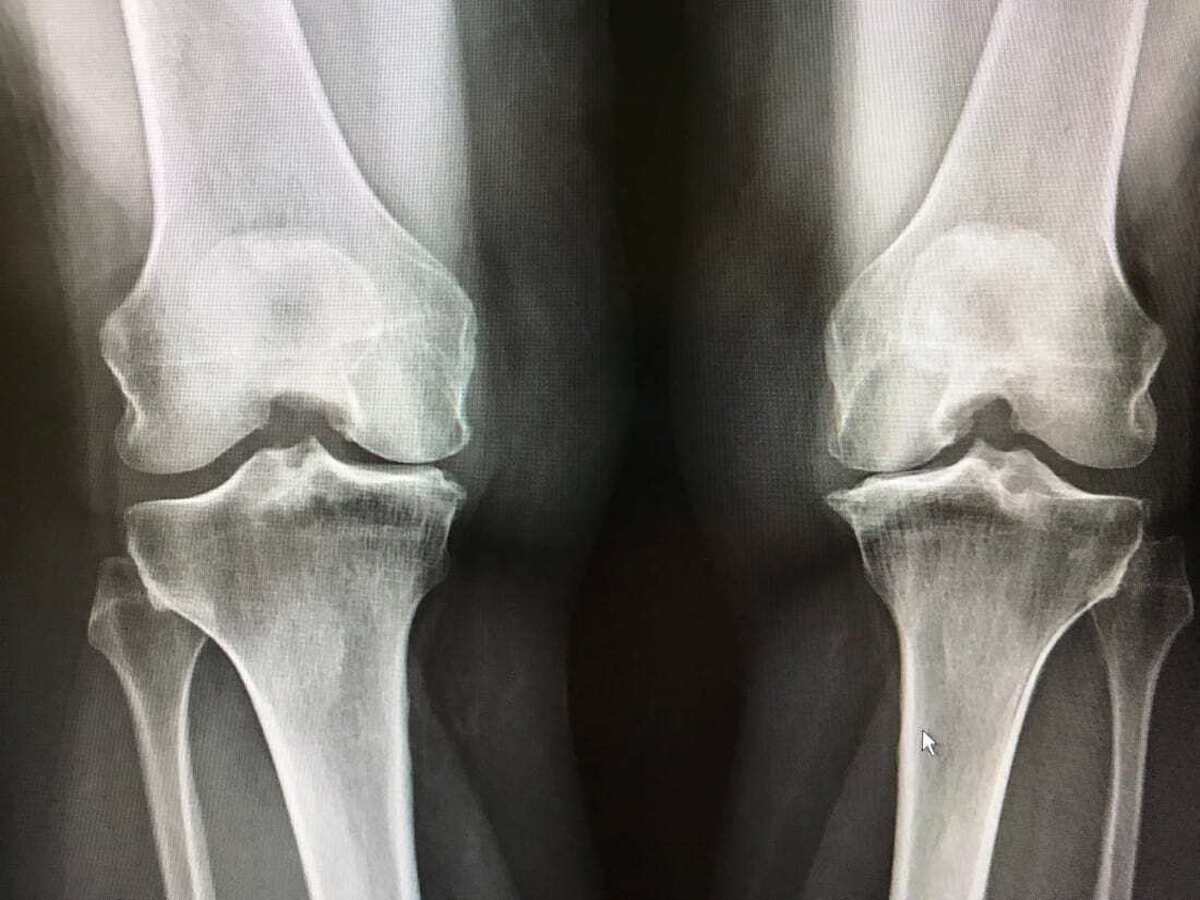

آشنایی با علائم اولیه آرتروز زانو

آرتروز زانو مشکلی شایع است که به‌تدریج موجب افت کیفیت زندگی افراد می‌شود. در این وضعیت مفصل زانو دچار التهاب و فرسایش شده و در هنگام فعالیت، فرد را دچار درد و ناراحتی شدید می‌سازد. آرتروز به‌طور عمده به‌دلیل آسیب به غضروف‌های مفصل زانو ایجاد می‌شود. در این صفحه به بررسی علائم اولیۀ آرتروز زانو، علل ایجاد آن، روش‌های تشخیص و درمان می‌پردازیم.

دانشیار دانشگاه علوم پزشکی مشهد گفت: آرتروز روی هر مفصلی تأثیر می‌گذارد؛ اما اغلب در زانوها، ران‌ ها، بخش پایین کمر، اتصالات کوچک انگشتان و قاعده‌ی انگشت شست و انگشت بزرگ پا بُروز می‌ کند؛ در کشورهای پیشرفته، میزان شیوع آرتروز زانو ١٣ درصد و در ایران ٢٠ درصد گزارش شده که با توجه‌ به بیشتر بودن جمعیت جوان ایران میزان شیوع این بیماری در افراد مسن ایران بسیار بیشتر است.